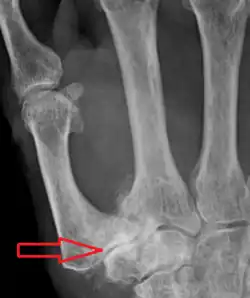

| Osteoarthritis of the trapeziometacarpal joint | |

Trapeziometacarpal osteoarthritis (TMC OA) is, also known as osteoarthritis at the base of the thumb, thumb carpometacarpal osteoarthritis, basilar (or basal) joint arthritis, or as rhizarthrosis.[3][1][2] This joint is formed by the trapezium bone of the wrist and the metacarpal bone of the thumb. This is one of the joints where most humans develop osteoarthritis with age.[4] Osteoarthritis is age-related loss of the smooth surface of the bone where it moves against another bone (cartilage of the joint).[3][5] In reaction to the loss of cartilage, the bones thicken at the joint surface, resulting in subchondral sclerosis. Also, bony outgrowths, called osteophytes (also known as "bone spurs"), are formed at the joint margins.[6]

TMC OA is diagnosed based on symptoms and signs.[8] Radiographs can confirm the diagnosis and the severity of TMC OA. Other diagnoses in this region include scaphotrapezial trapezoid arthritis and first dorsal compartment tendinopathy (De Quervain syndrome) although these are usually easy to distinguish.